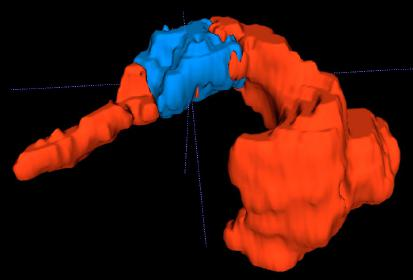

Creating large-scale and well-annotated datasets to train AI algorithms is crucial for automated tumor detection and localization. However, with limited resources, it is challenging to determine the best type of annotations when annotating massive amounts of unlabeled data. To address this issue, we focus on polyps in colonoscopy videos and pancreatic tumors in abdominal CT scans; both applications require significant effort and time for pixel-wise annotation due to the high dimensional nature of the data, involving either temporary or spatial dimensions. In this paper, we develop a new annotation strategy, termed Drag&Drop, which simplifies the annotation process to drag and drop. This annotation strategy is more efficient, particularly for temporal and volumetric imaging, than other types of weak annotations, such as per-pixel, bounding boxes, scribbles, ellipses, and points. Furthermore, to exploit our Drag&Drop annotations, we develop a novel weakly supervised learning method based on the watershed algorithm. Experimental results show that our method achieves better detection and localization performance than alternative weak annotations and, more importantly, achieves similar performance to that trained on detailed per-pixel annotations. Interestingly, we find that, with limited resources, allocating weak annotations from a diverse patient population can foster models more robust to unseen images than allocating per-pixel annotations for a small set of images. In summary, this research proposes an efficient annotation strategy for tumor detection and localization that is less accurate than per-pixel annotations but useful for creating large-scale datasets for screening tumors in various medical modalities.